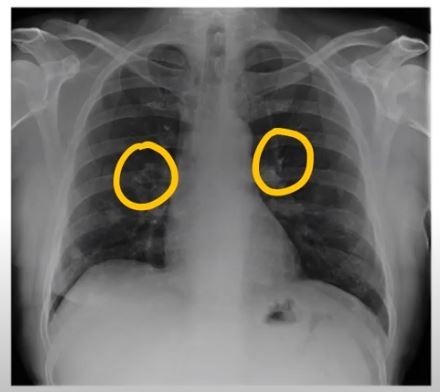

폐렴 증상 폐렴은 폐의 세균, 바이러스, 곰팡이 등 감염으로 인해

폐포(폐 속의 공기 주머니)에 염증이 생기고, 고름이나 액체가 차는 질환입니다.

이로 인해 산소 교환이 원활하지 못해 호흡곤란, 기침, 발열 등이 나타나죠.특히 영유아, 고령층, 면역력이 약한 사람에게서 더 위험하며